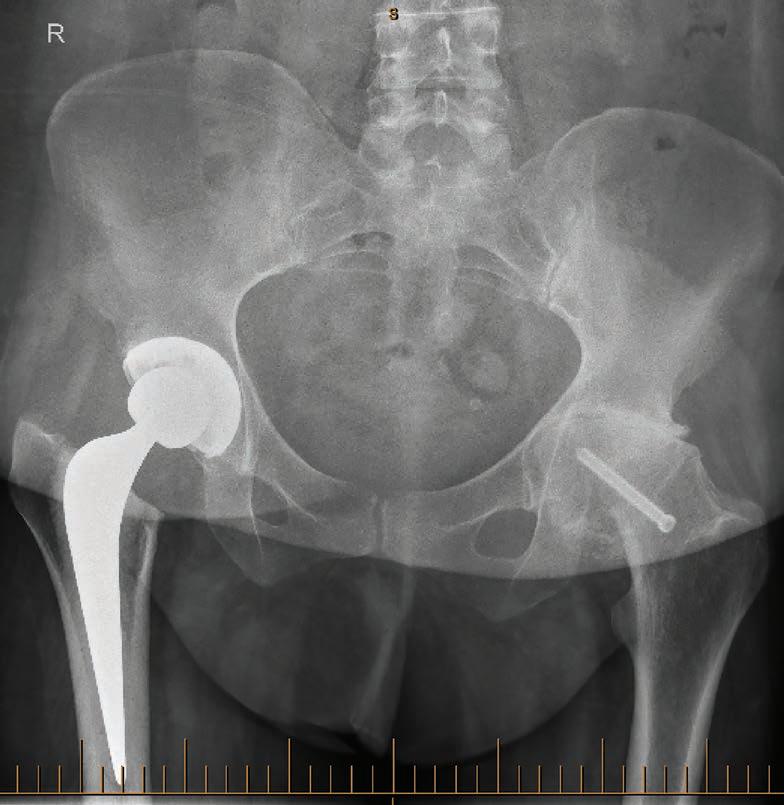

WINPREMIUM WINESFROMWEST C A P E EWOH 16 CONNECT WITH US /medicalforumwa /MedicalForum_ /medical-forum-wa-magazine info@mforum.com.au www.mforum.com.au

5 Bulk-billed genetic carrier screening Dr Minette Saad 40 Mammographic breast density Dr Eric Khong 42 Menopause & women’s health, wellbeing & productivity Dr Purity Carr & Dr Christabel Samy Guest Columns 10 Call for more inclusive primary care Dr Roanna Lobo 31 Concussion guidelines support safe decisions Dr Sarah Hellewell 45 Hormonal management in endometriosis Dr Jennifer Pontré & Dr Bernadette McElhinney 51 Diet therapies & IBS Ele Stojanoska 52 Robotic-assisted hip & knee replacement outcomes Dr Dan Marshall 55 Uterine fibroid embolisation Dr William Ormiston 46 Ovarian endometriomas Dr Sean Copson 49 Ovarian reserve Dr Santanu Baruah 37 Age-old problems set to haunt Mark Woodland

Orthopaedic roles take shape

A doctor and nurse have been appointed to lead roles at the new Orthonova Orthopaedic Hospital to be built on the St John of God Murdoch Hospital campus by late 2026.

Dr Alex Swann will be Orthonova Commissioning Director – Medical, a part-time role on top of his existing position as Director of Anaesthetics and Pain Management at SJOG Murdoch.

Kimberley Montgomery will start as Commissioning Director – Nursing, moving from her former position at SJOG Murdoch where she is Director of Nursing, Specialist Services.

Orthonova will be the first specialist orthopaedic hospital of its kind in WA. Under a joint venture, 24 orthopaedic surgeons will join with St John of God Health Care to develop and operate the hospital.